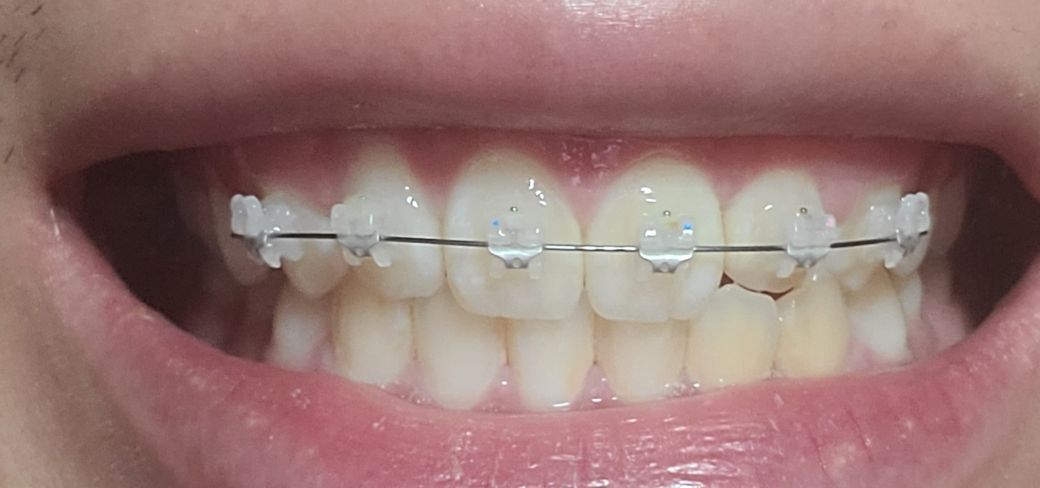

앞니 약간 벌어짐 과 두번째앞니가 들어가 있어서 부분교정중 입니다

교정전부터 뼈 비대칭 때문에 치아중심선이 조금 안맞은 상태였는데 두번째앞니 전방으로 빼고있는 상태인데 두번째 앞니를 앞으로 빼다보면 교정완료후에 치아중심선이 더 안맞아보이거나 틀어질수도 있나요?

• 1번 째 사진